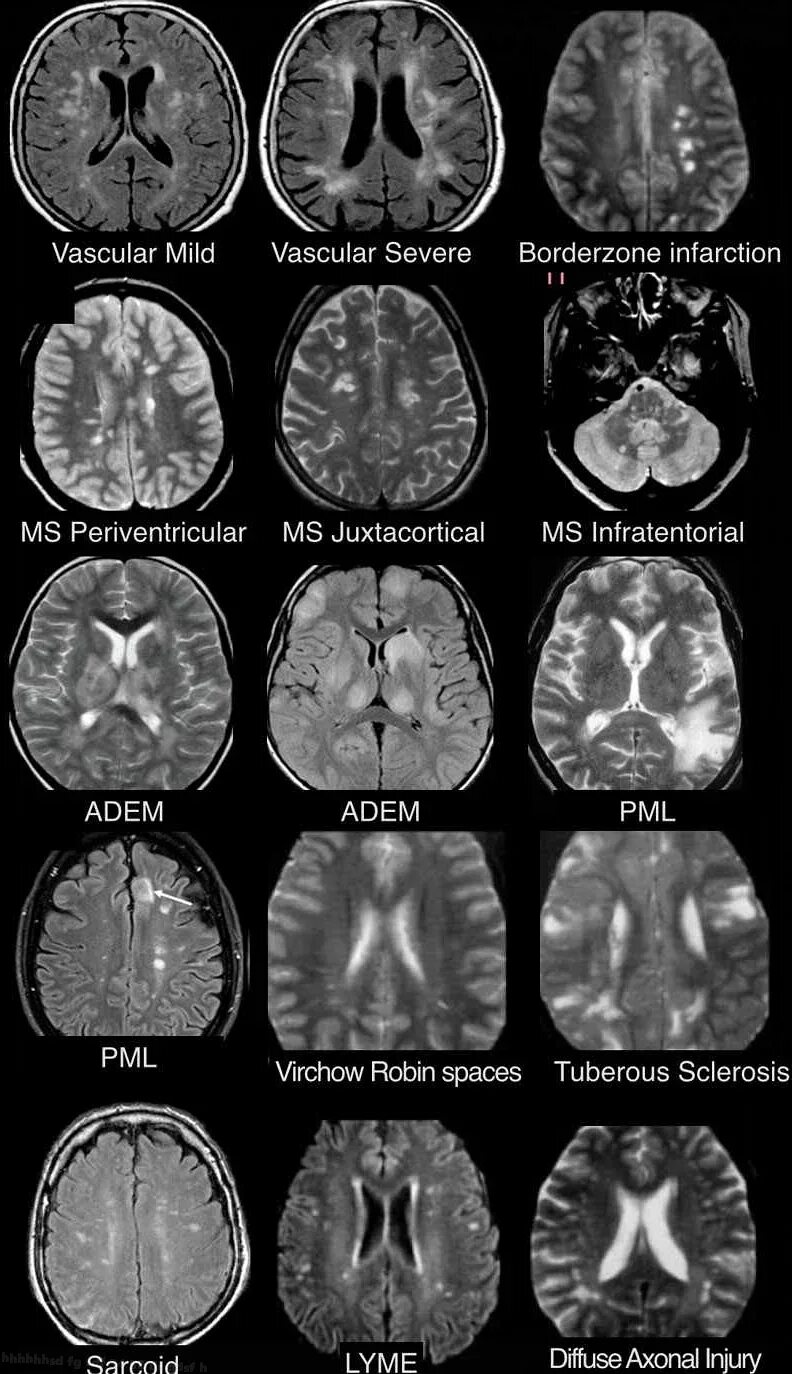

Белые очаги в головном мозге